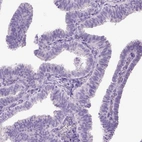

Immunohistochemistry analysis in human urinary bladder and fallopian tube tissues using HPA022261 antibody. Corresponding CYP24A1 RNA-seq data are presented for the same tissues.